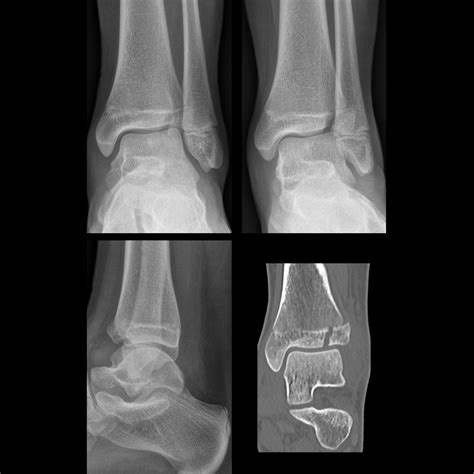

These fractures typically occur in adolescents whose growth plates are still active but nearing closure. The most frequent areas for a Salter Harris Type II injury include the distal radius (the wrist) and the distal tibia (the ankle). The injuries are usually caused by:

Diagnosing a Salter Harris Type II fracture requires a clinical evaluation followed by medical imaging. Physicians will look for tenderness specifically localized to the growth plate area, accompanied by swelling and a potential deformity if the bone is significantly displaced. The following table highlights key diagnostic comparisons within the Salter-Harris system.

Radiographic evidence is crucial. While a standard X-ray will usually reveal the Salter Harris Type II fracture, subtle cases might require comparing the injured limb with the uninjured side. In some instances, the fracture may be nondisplaced, making it look like a simple soft tissue injury; however, if there is persistent pain, follow-up imaging is mandatory.